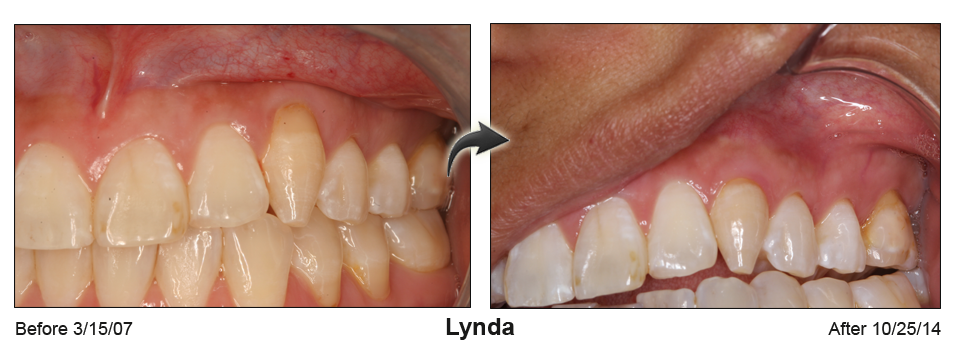

A rejuvenated smile and no sensitive roots

Gum recession not only ages your smile, it creates causes painful sensitivity to temperatures and sweets. Based in Houston & Baytown, TX, Dr. Khalid uses minimally invasive microsurgical techniques to perform cutting edge gum recession treatment and gum grafts.

Receding gums can make anyone look older

Receding gums can make anyone look older, often cause tooth sensitivity and may lead to tooth loss. Gum recession can be caused by excessive tooth brushing, gum disease or the normal aging process.

"Many people are unaware of the condition until their teeth become sensitive to cold temperatures because of root exposure. Others may be concerned by the unsightly appearance of their receding gums." says Dr. Khalid.